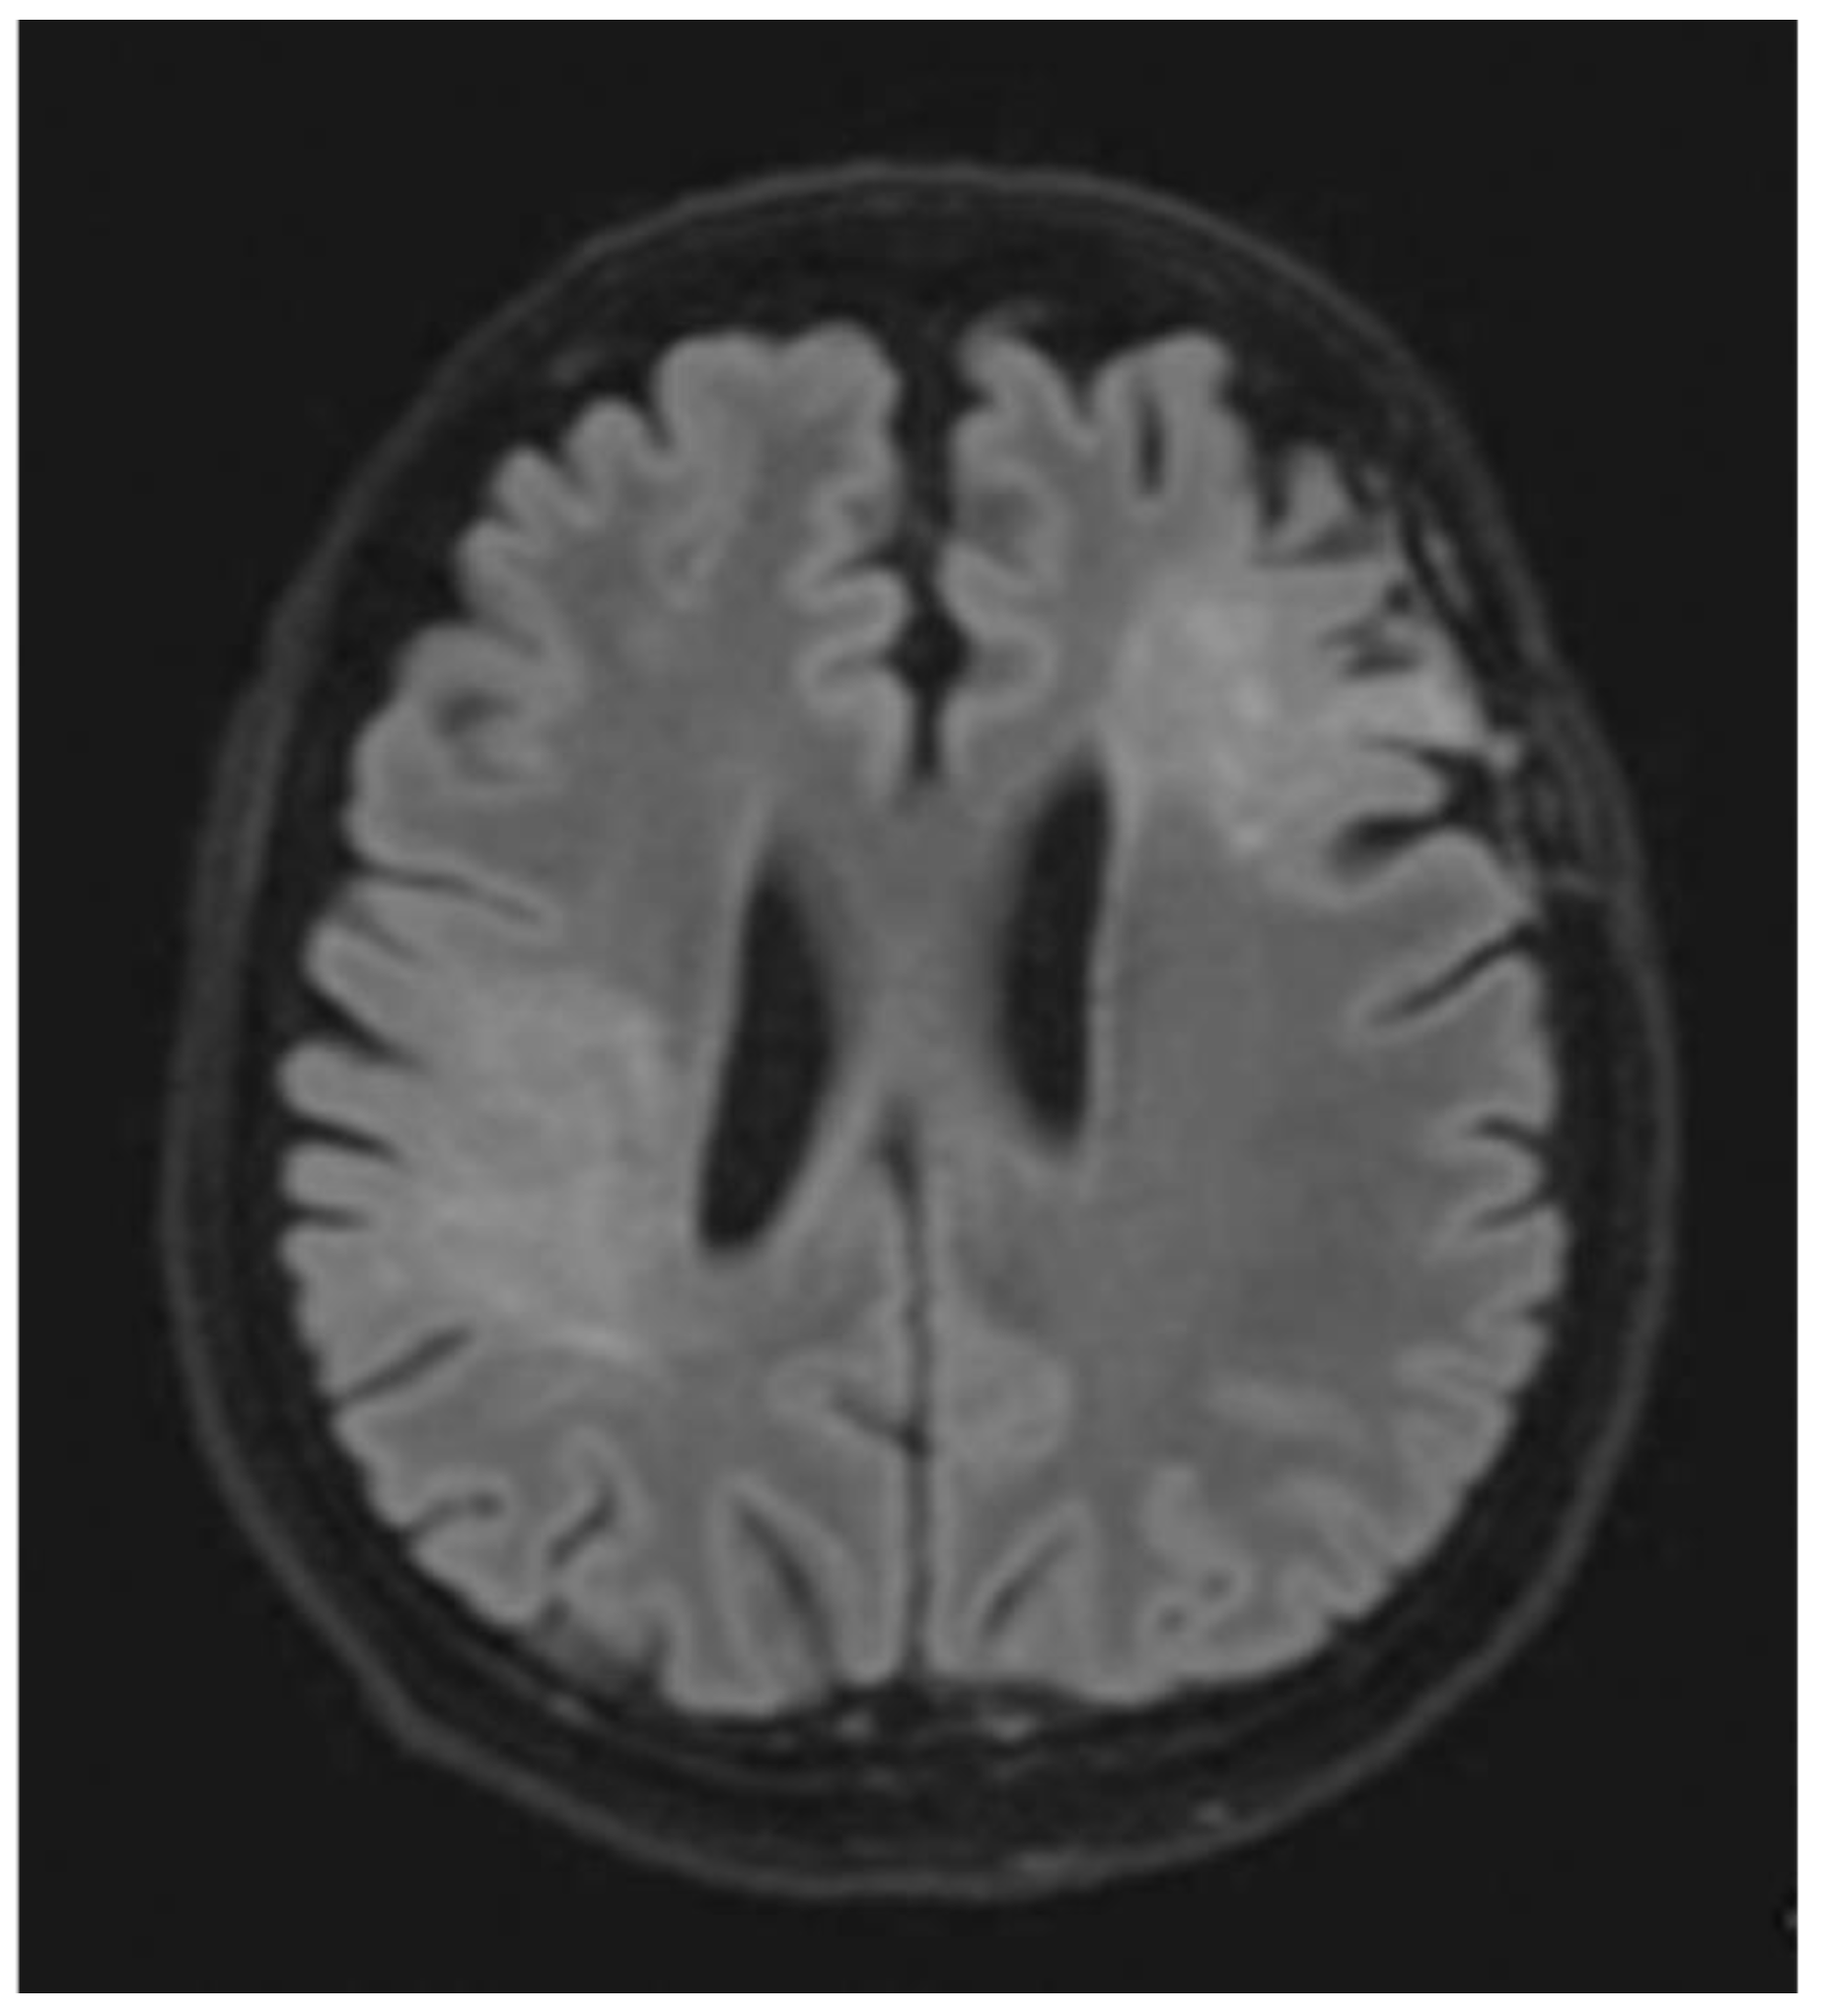

Figure 9. Follow-up axial postcontrast FLAIR images of the same patient after treatment with steroids at 2 and 6 months (A and B, respectively), showing decreased size of the lesion without residual enhancement.

Taking into consideration each patient’s brain MRI and spinal MRI, if available, dissemination in space (DIS), according to the McDonald criteria, was found in 31 out of the 32 patients (96.9%). The only patient whose MRIs did not demonstrate DIS was the one with a brain MRI typical of tumefactive MS. The patient received a high dose of intravenous methylprednisolone. After follow-up, the lesion decreased in size and no new lesions were detected (Figure 8 and Figure 9).